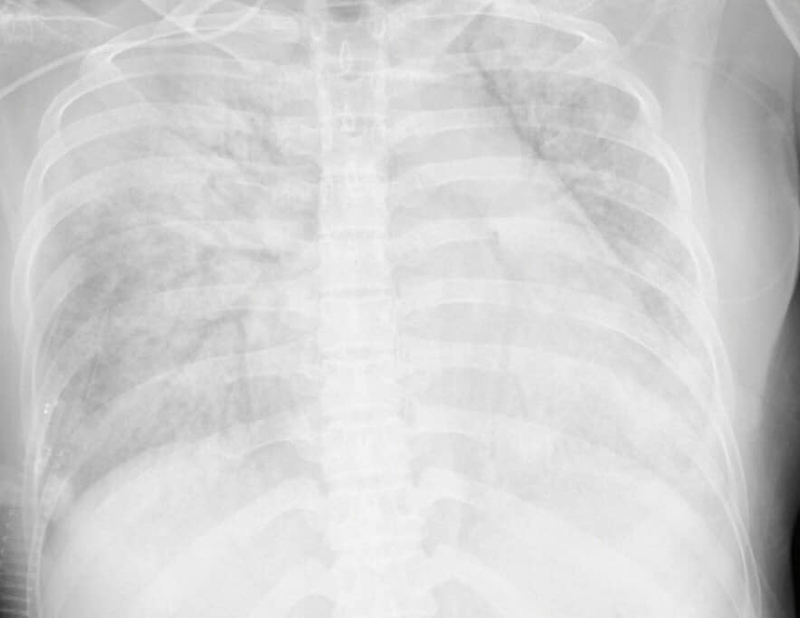

| Hình ảnh phim chụp phổi của sản phụ C. Ảnh: BVCC. |

Ca mổ được thực hiện thành công. Sau mổ, em bé được chuyển về khu vực Hồi sức Nhi an toàn. Vấn đề khó nhất là hồi sức mẹ vì tổn thương phổi do Covid-19 nặng, nồng độ oxy trong máu giảm rất thấp. Bệnh nhân được chăm sóc tích cực, thở máy, truyền máu, lọc máu liên tục bằng quả hấp phụ Cytokines trong 5 ngày…